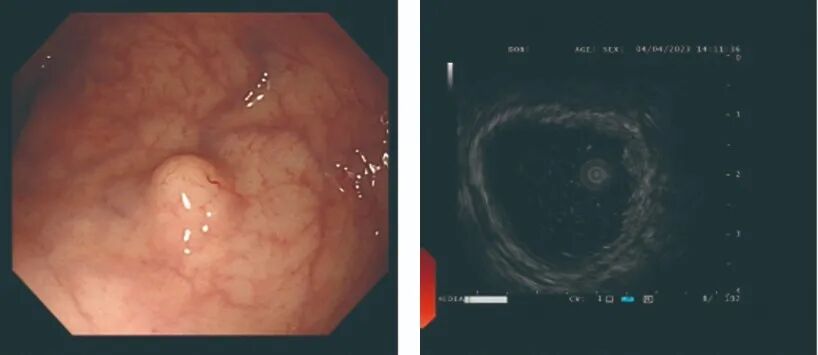

小探头超声胃镜:

让躲在粘膜下的病变清晰可辨!